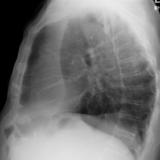

LUL Collapse Case 1 Lateral

Date: 02/19/2004

Views: 3839